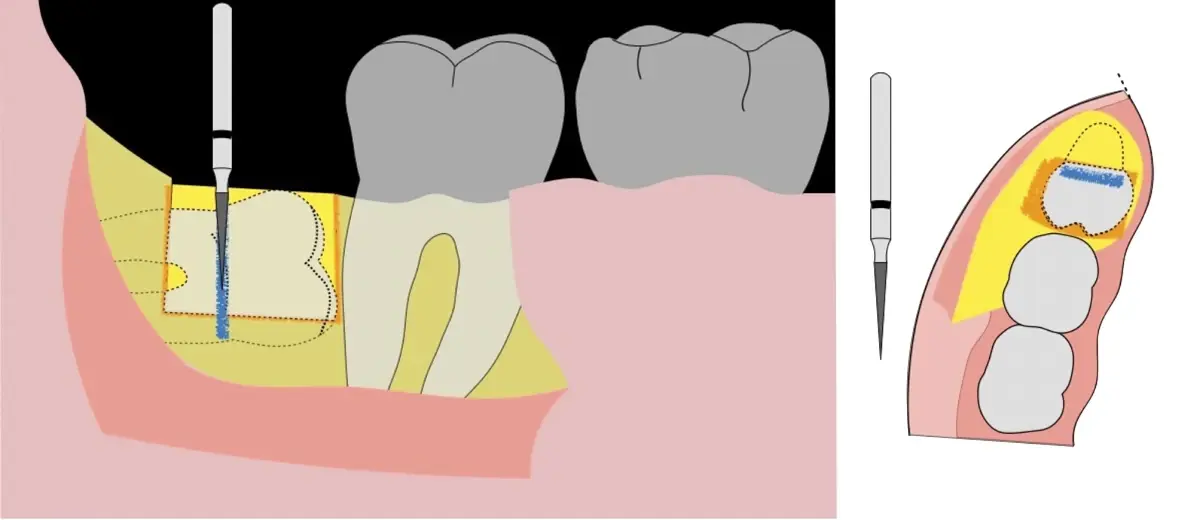

Es imprescindible conocer la ubicación de la tercera molar. Se puede emplear, adicionalmente a la evaluación clínica, herramientas radiográficas (panorámica y periapical) y tomográficas (Cone beam) para determinar la posición, grado de retención y proximidad a estructuras vecinas de riesgo como el nervio dentario inferior y así evitar lesiones (Figura 1).

El procedimiento se inicia colocando anestesia troncular para bloqueo del nervio dentario inferior y sus ramas. Luego, se establecerá el diseño de acceso según la disposición de la molar a extraer. Para fines didácticos, se explicará cómo se realizaría la extracción de la molar de la Figura 1: se realiza una incisión horizontal a nivel de la zona retromolar hasta llegar a distal de la segunda molar, continuándose con una incisión intrasurcular hasta mesial de la segunda molar, finalizando con una incisión vertical a espesor total hasta llegar a la línea mucogingival (Figura 2).